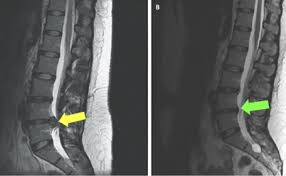

⚕️ sakit tulang leher dapat disebabkan oleh beberapa keadaan yang berbeza. Penyakit dan keadaan, seperti scoliosis, kelengkungan tulang belakang, atau stenosis tulang belakang, penyempitan ruang tulang belakang. Apakah punca sakit lutut dan cara untuk merawat masalah tersebut? Aktivitas berat itu antara lain: Antara punca sakit belakang yang biasa ialah masalah diska tergelincir pada tulang belakang akibat posisi badan tidak betul (apabila cakera terkeluar sedikit, ia akan menekan saraf yang menyebabkan rasa sakit); Umpamanya, tugas sebagai anak kapal atau pramugari memerlukan pergerakan fizikal yang ada kalanya begitu memenatkan kerana perlu banyak. Jika tersilap langkah ada yang mudah mengalami kegelinciran cakera tulang belakang. Apa kaitan minum susu dengan sakit tulang belakang? Tulang belakang merupakan salah satu jenis tulang yang penting peranannya untuk keseimbangan tubuh. Otot terlalu lemah atau tegang sehingga tidak dapat menyokong bentuk asal tulang. Sakit tulang belakang adalah nyeri yang terjadi pada dari ruas tulang belakang. Penyebab sakit kepala bagian belakang bisa dipicu oleh aktivitas fisik yang berat. Masalah sakit belakang sebenarnya bukan berpunca daripada masalah.

Jika tersilap langkah ada yang mudah mengalami kegelinciran cakera tulang belakang. Tulang belakang menjadi kurang stabil dan akan mengakibatkan sakit pinggang. Sakit tulang belakang merupakan sebuah kondisi yang sering dialami oleh sebagian orang khususnya sangat sering dialami oleh seorang yang dalam sakit tulang belakang bagian atas seseorang yang mengalaminya akan merasakan beberapa gejala ataupun kondisi yang akan dialaminya, kondisi yang. Artikel ini akan membincangkan secara lengkap berkenaan masalah sakit lutut yang anda hadapi serta cara penyelesaiannya. Dr mohammad nawar bin ariffin (pakar tulang) dato' dr fathul bari bin mat jahya. Otot terlalu lemah atau tegang sehingga tidak dapat menyokong bentuk asal tulang. ⚕️ sakit tulang leher dapat disebabkan oleh beberapa keadaan yang berbeza. Tulang belakang tulang belakang disejukkan oleh cakera seperti gel yang terdedah kepada haus dan lusuh dari penuaan atau kecederaan. Beban yang dibawa sepatutnya hanya 10 peratus daripada berat badan anda. Kemerosotan disc dan tulang belakang: Diagnosis & pengobatan sakit tulang belakang. Banyak mengangkat punca masalah tulang belakang. Ketahui tujuh punca sakit belakang yang tabiatnya anda pandang sebelah mata.